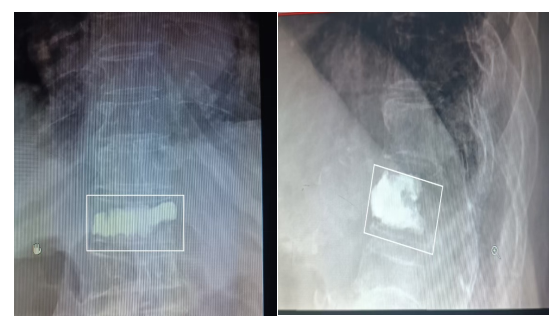

术前X光片显示:T12压缩骨折,椎体压缩,变扁

入院第二天,骨科团队为李奶奶行PVP(经皮椎体成形术)微创手术治疗,手术仅仅用时10多分钟便顺利完成,伤口为一个小小的针眼。

术后X光片显示:椎体高度恢复

麻醉完全清醒后即可翻身起床,术后第1天就佩带腰围下地行走,疼痛明显缓解,术后第3天就出院了。同时,微创手术还纠正了胸椎T12骨折导致的椎体高度丢失,防止了老人家驼背的加重。